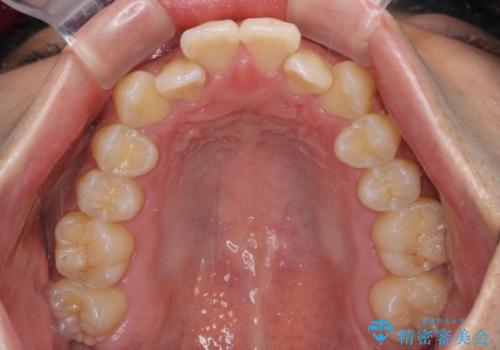

- 前歯のデコボコを気にして来院された患者様です。

歯列としてはワイヤー装置でもインビザラインでも対応可能でしたが、インビザラインが苦手とする上顎側切歯(真ん中から2番目の歯)の舌側転位が顕著でした。

治療の確実性を上げるために、インビザライン開始前に上顎のワイヤー装置にて舌側転位を解消し、その後インビザラインにて矯正治療を行うこととしました。

前歯のデコボコが早めに改善され、スムーズに治療を終えることができました。